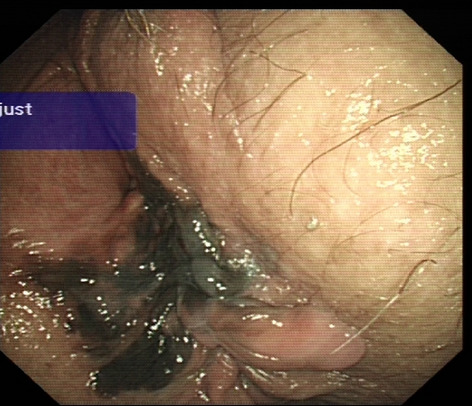

Until now there have been early attempts at producing advanced laparoscopic systems but these have been cumbersome and limited in their engineering. We present a revolutionary new advanced laparoscopic instrumentation system called ArtiSential. The ArtiSential instruments include bipolar forceps, Maryland dissector, monopolar spatula, monopolar hook, needle holder, with more on the way. They allow a wide range of articulating movement through 7 degrees of freedom that can mimic the dexterity of robotic platforms (Fig. 1). Traditional laparoscopic instruments have limited range of movements but these instruments allow for complex articulating movements in different planes which can be further exploited around the fulcrum of the port. This additional articulation means that there is better access to difficult part of anatomy. Furthermore, there is tactile feedback on the instrument handset which is lightweight and disposable.

Our initial series of cases include pelvic colorectal surgery and demonstrate the advantages of articulating instruments (Fig. 2). Further, we demonstrate that there is a learning curve to these instruments to maximise their benefit during complex procedures. We suggest adopting the formal training programme which includes a period of dry lab training before embarking on clinical cases so that surgeons may truly benefit from these advanced instruments. This also allows for safer introduction of new technology.

Advanced laparoscopic instruments such as ArtiSential should be used to make challenging aspects of laparoscopic surgery more accessible. These are not substitute for all straight instruments but best used to maintain precision during difficult manoeuvres in combination with traditional instruments.